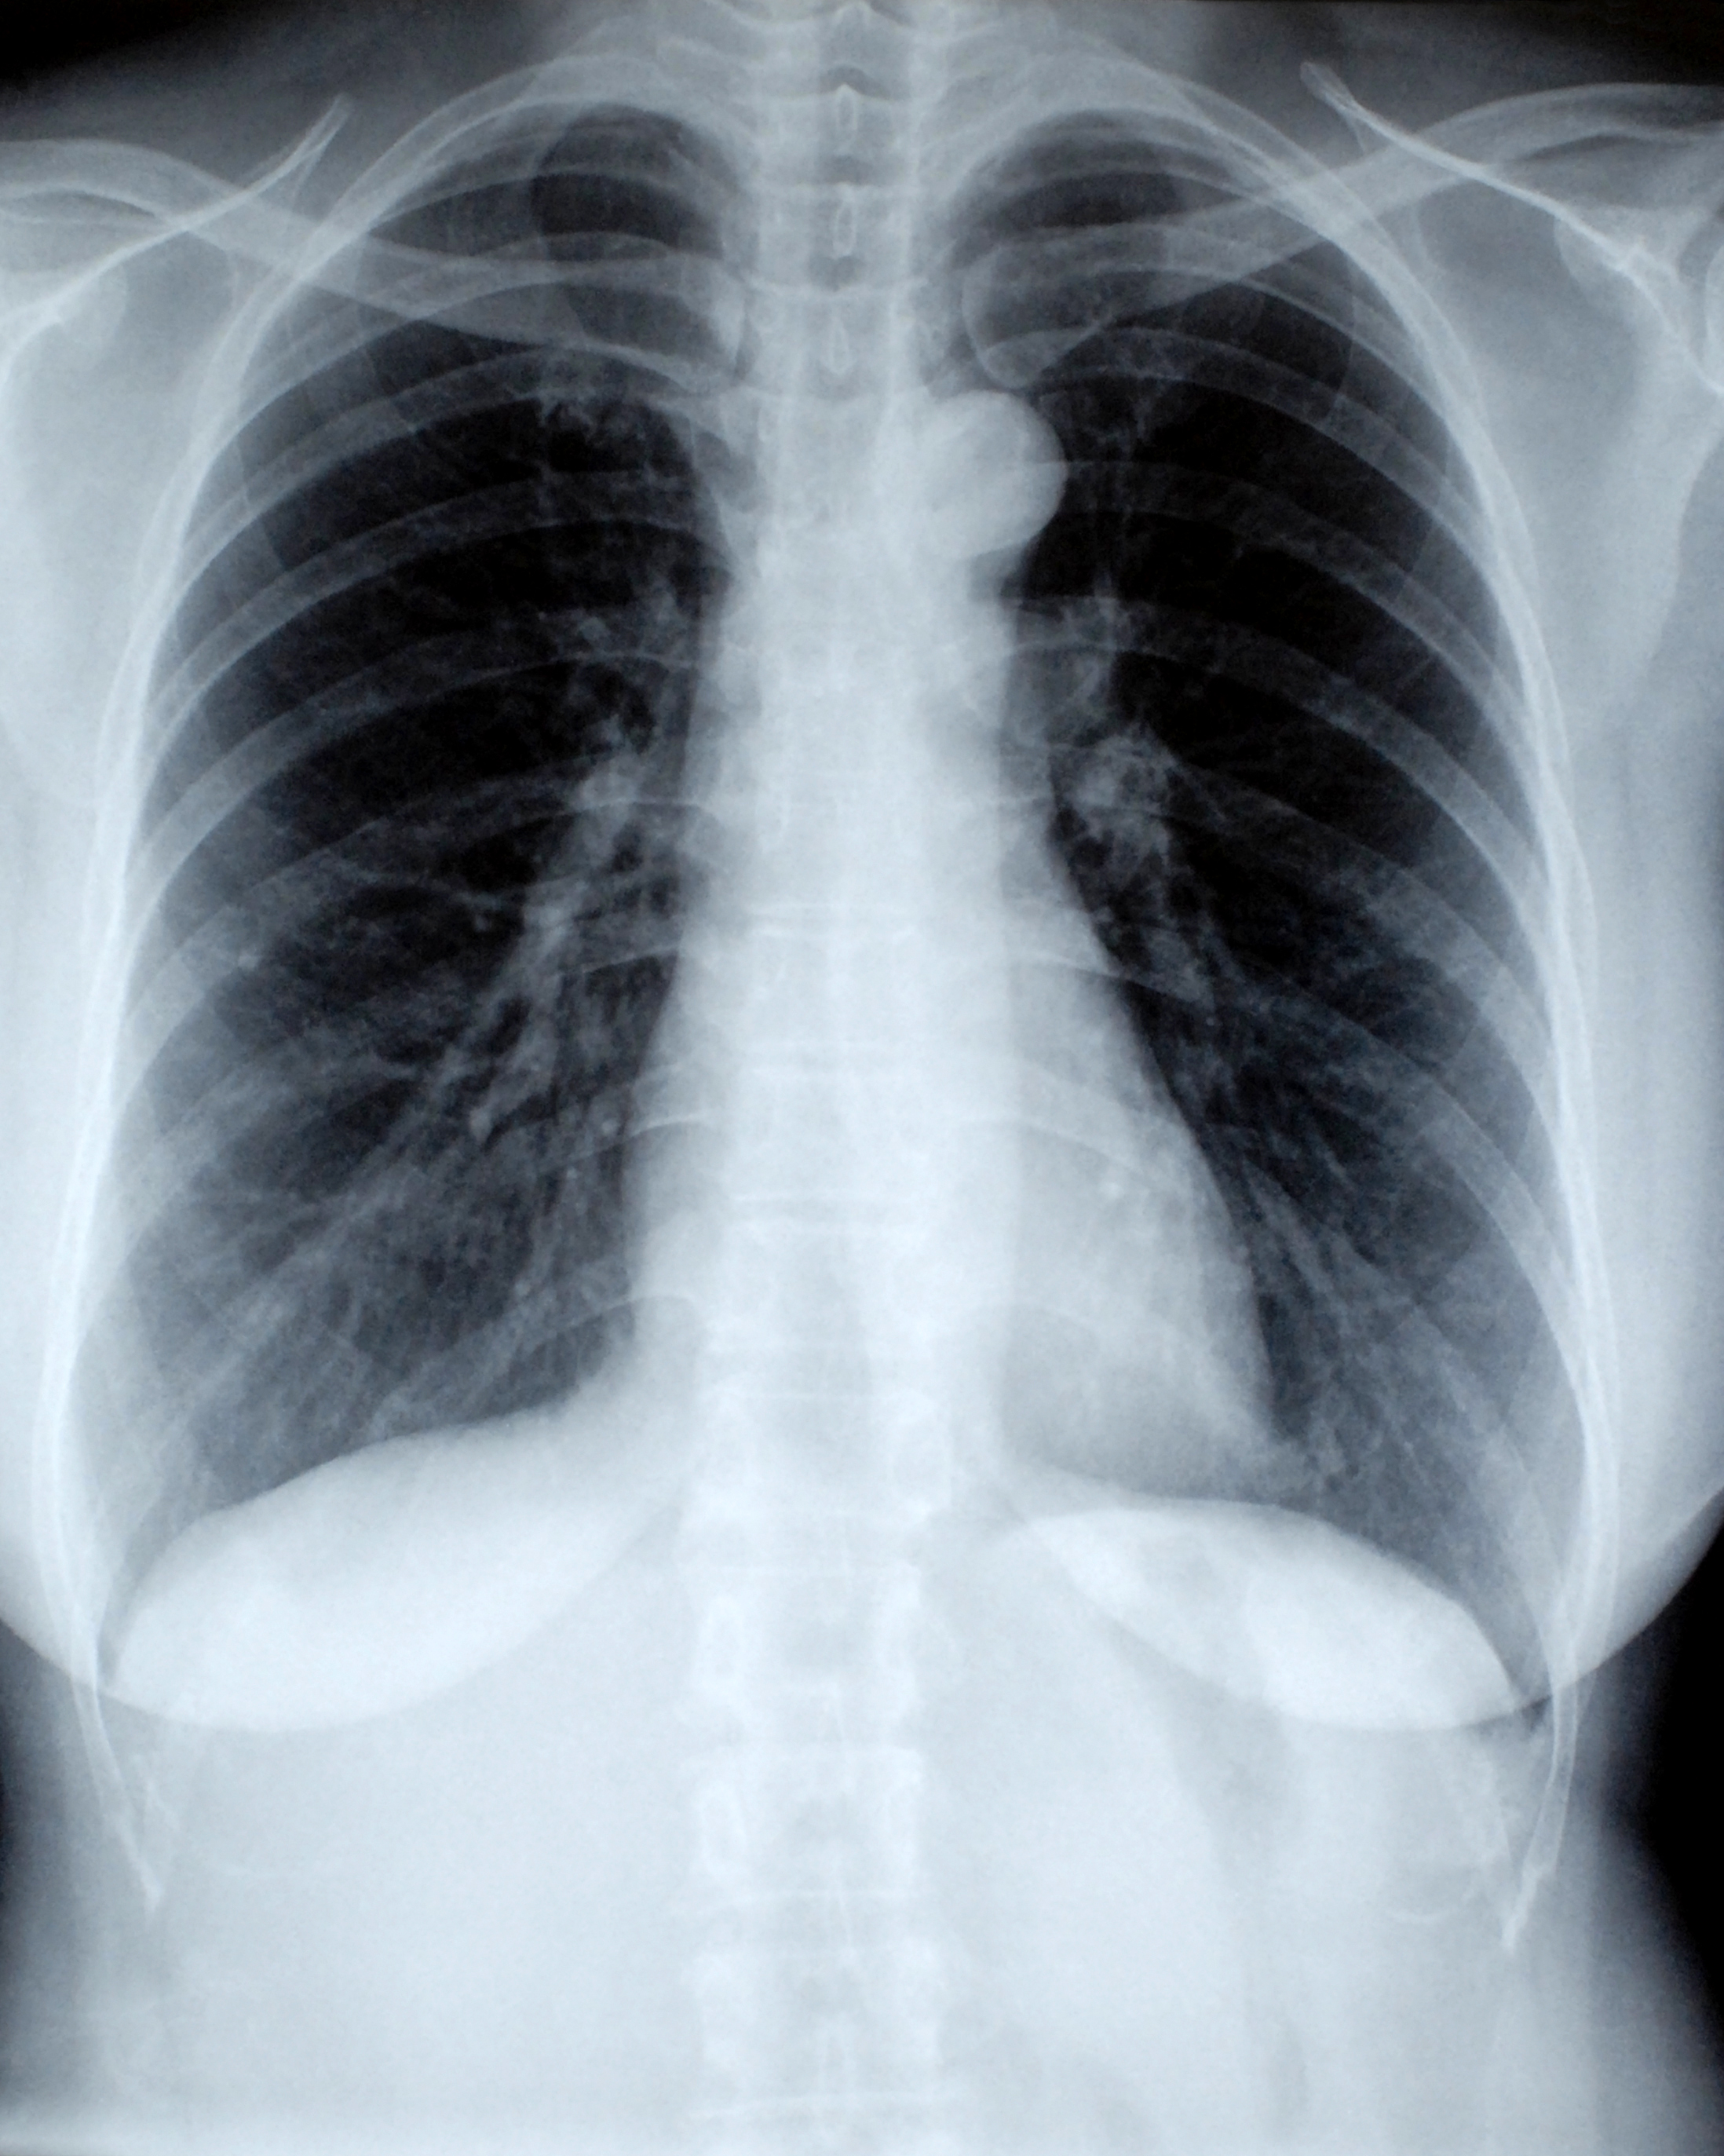

A deep learning model to classify chest X-rays into COVID, Pneumonia, and Normal cases using CNNs.

View on GitHub View on Streamlit

“Interactive demo that classifies chest X-rays as Pneumonia vs No Finding using a fine-tuned ResNet-18 and explains its decision with Grad-CAM heatmaps.